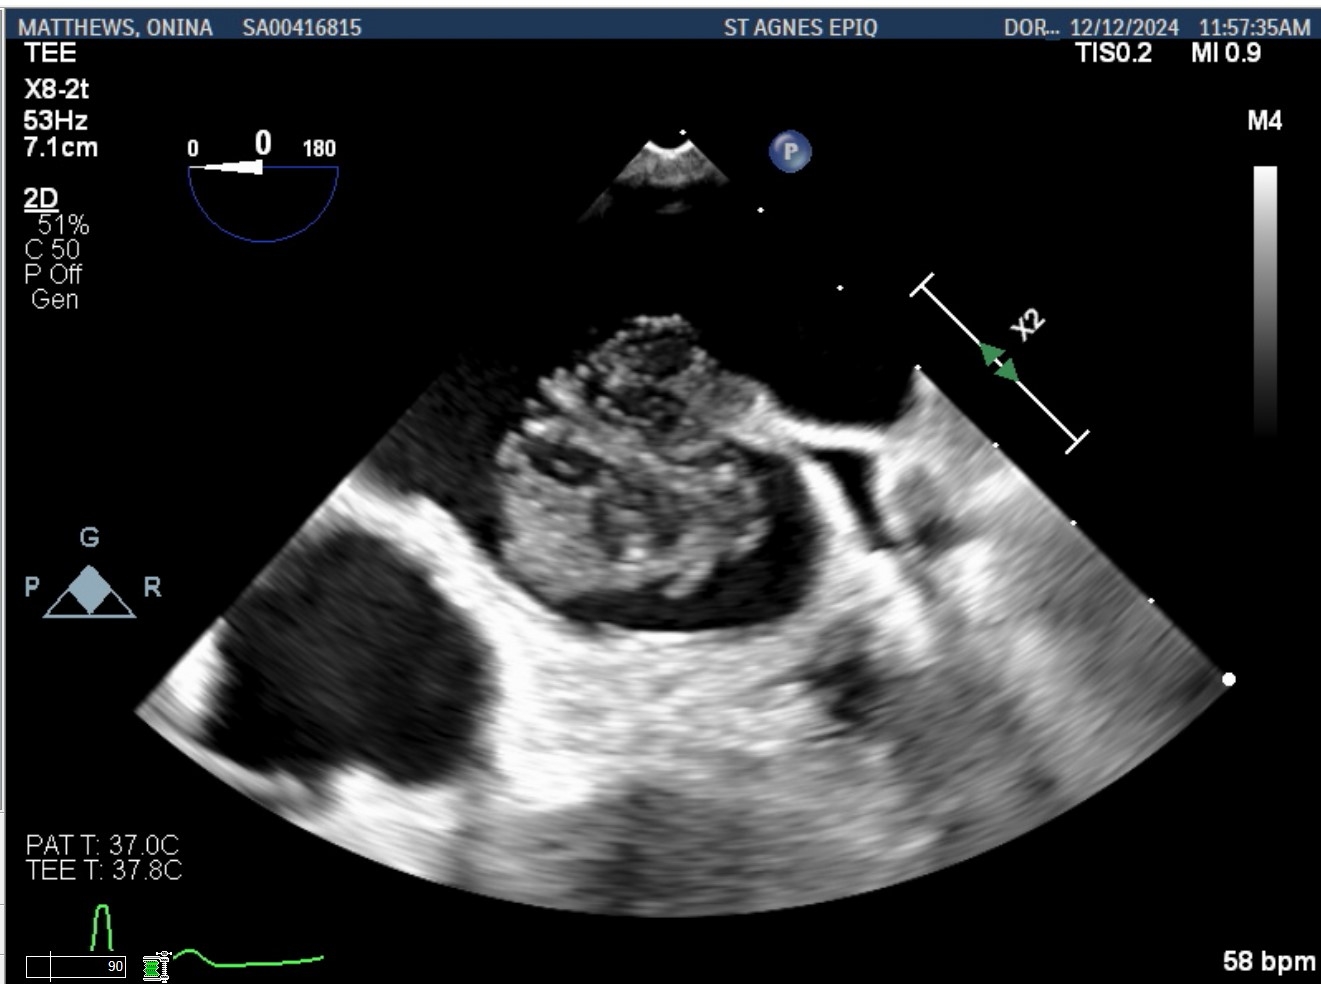

Case Presentation: A 70-year-old woman was evaluated for a TAVR workup due to recent worsening of fatigue and dyspnea. Physical examination revealed grade three ejection systolic murmur with diminished S2 and severe aortic stenosis was noted on transthoracic echocardiogram. Cardiac CT showed an atrial mass. Transesophageal echocardiography demonstrated a heterogenous left atrial mass measuring 2.7 x 2.4 cm; originates from the tip of the Coumadin ridge, independently mobile with a dandelion-like gelatinous appearance, and did not take up Definity contrast (Figures 1, 2, 3). The patient underwent surgical aortic valve replacement with mass excision through the interatrial septum. Pathologic examination revealed 2.5 x 2.2 x 1.5 cm tan-white, villous, gelatinous soft tissue consistent with fiberoelastoma.